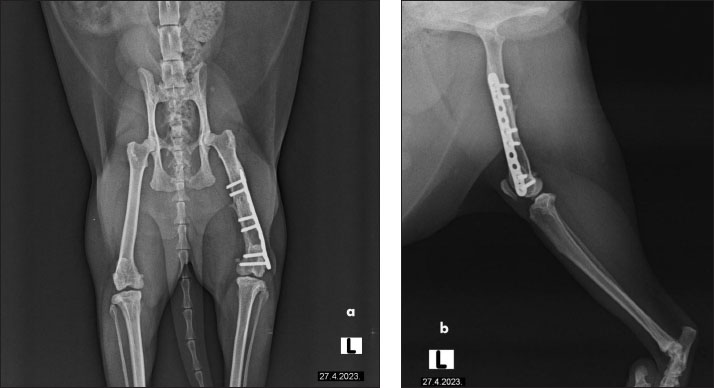

The cat had undergone orthopedic surgery 4 years ago, during which a plate was placed due to a femoral fracture (Fig. 2). Despite the surgery, the patient continued to show signs of discomfort, necessitating further diagnostics and therapy. During the examination at the radiology clinic, the cat showed signs of lameness and pain. The clinical examination revealed muscle atrophy of the left leg and pain on extension and flexion. Radiographic imaging of the pelvis and left femur revealed changes associated with the implant. Removal of the implant was recommended and subsequently performed. Figure 3 shows the radiographs of the cat’s left femur post-plate removal, showing 1 screw remaining in situ. Increased transparency in the medullary cavity indicates the need for LT to enhance healing and promote tissue regeneration.

Fig. 3. Radiographs of a cat’s left femur showing (a) a ventrodorsal and (b) a mediolateral view post-plate removal, with one screw remaining in situ. Increased medullary cavity transparency highlights the need for LT to support bone healing and tissue regeneration.